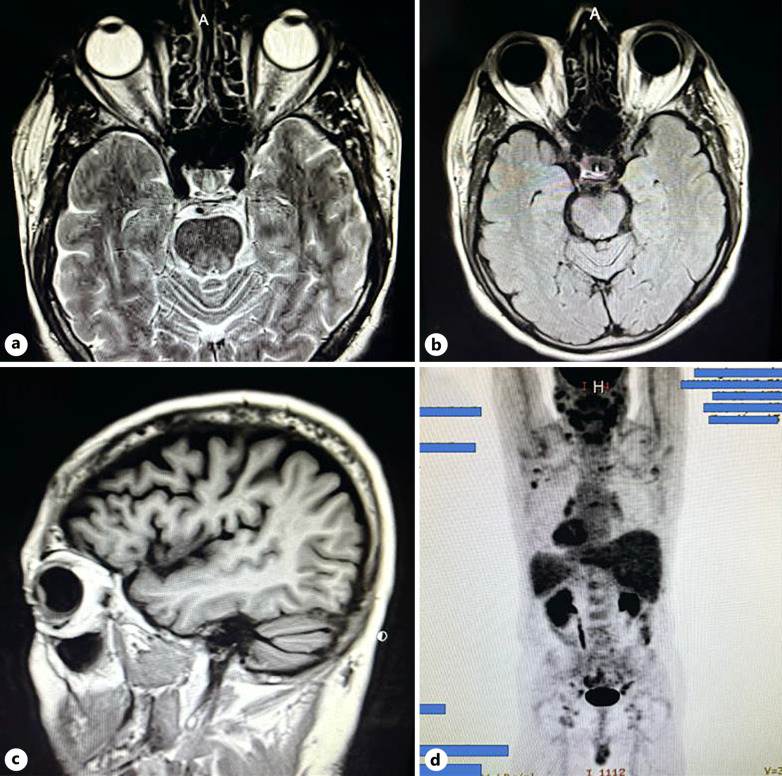

Introduction: Bilateral hemorrhagic hypopyon, also known as candy cane hypopyon, is an extremely rare presentation which we report as a unique case in association with intraocular mantle cell lymphoma (MCL).

Case presentation: A 63-year-old white male presented with a 3-week history of conjunctival injection OS that was unresponsive to erythromycin ointment and topical steroids, in the setting of recently discovered diffuse lymphadenopathy and malaise. On presentation, he was found to have bilateral hemorrhagic hypopyon. Lymph node biopsy was diagnostic of MCL, and subsequent anterior chamber paracentesis confirmed intraocular MCL. The patient was put into remission with intravitreal rituximab injections, systemic chemotherapy, and external beam radiation.

Conclusion: Cases of MCL with ocular involvement typically involve ocular adnexal structures, and seldom involve the uvea. Furthermore, this patient represents an extremely unusual case in his presentation with a hemorrhagic hypopyon.